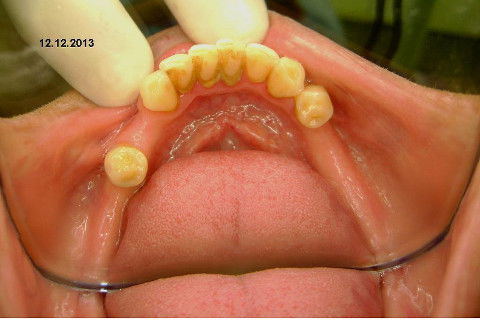

Cirurgia realizada hoje de manhã...No planejamento percebi medindo espessura do rebordo com especímetro que as medidas não estavam muito boas, ou o ideal, em torno de 4,5 a 5 mm ate´o terço médio do rebordo e melhorava no final, com 6 a 7 mm. Optei então por uma pequena expansão usando os expansores rosqueáveis. Aconteceu uma pequena fenestração na hora da fixação dos implantes, especialmente na região do 22 que fraturou o início da tábua óssea, mas não me preocupei porque não foi mais do que 2 mm de fratura em direção apical, o implante ficou infraósseo e com boa estabilidade (60 N no 21 e 40 N no 22). Esta fratura tb não deixou osso completamente solto, foi do tipo galho verde, deixei em posição e suturei normalmente. Só não fiz e nem estava planejado carga imediata mesmo, mais pelo motivo da oclusão inadequada do caso.

Fotos do caso